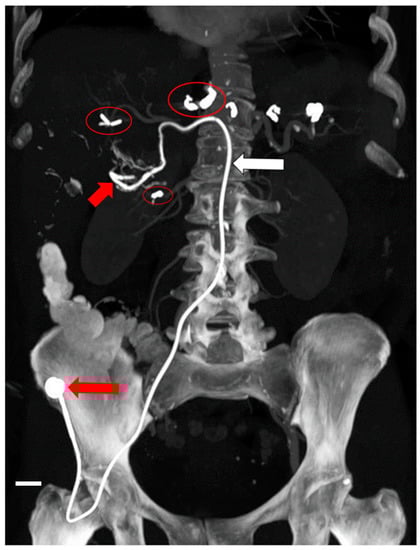

- Chevallier, O.; Mvouama, S.; Pellegrinelli, J.; Guillen, K.; Manfredi, S.; Ghiringhelli, F. Percutaneous Implantation of a Microcatheter-Port System for Hepatic Arterial Infusion Chemotherapy of Unresectable Liver Tumors: Technical Feasibility, Functionality, and Complications. Diagnostics 2021, 11, 399. [Google Scholar] [CrossRef]

- Favelier, S.; Germain, T.; Genson, P.Y.; Cercueil, J.P.; Denys, A.; Krausé, D.; Guiu, B. Anatomy of liver arteries for interventional radiology. Diagn. Interv. Imaging 2015, 96, 537–546. [Google Scholar] [CrossRef]

- Deschamps, F.; Rao, P.; Teriitehau, C.; Hakime, A.; Malka, D.; Boige, V.; Ducreux, M.; Elias, D.; Goere, D.; de Baere, T. Percutaneous femoral implantation of an arterial port catheter for intraarterial chemotherapy: Feasibility and predictive factors of long-term functionality. J. Vasc. Interv. Radiol. 2010, 21, 1681–1688. [Google Scholar] [CrossRef]

- Herrmann, K.A.; Waggershauser, T.; Sittek, H.; Reiser, M.F. Liver intraarterial chemotherapy: Use of the femoral artery for percutaneous implantation of catheter-port systems. Radiology 2000, 215, 294–299. [Google Scholar] [CrossRef]

- Tanaka, T.; Arai, Y.; Inaba, Y.; Matsueda, K.; Aramaki, T.; Takeuchi, Y.; Kichikawa, K. Radiologic placement of side-hole catheter with tip fixation for hepatic arterial infusion chemotherapy. J. Vasc. Interv. Radiol. 2003, 14, 63–68. [Google Scholar] [CrossRef]